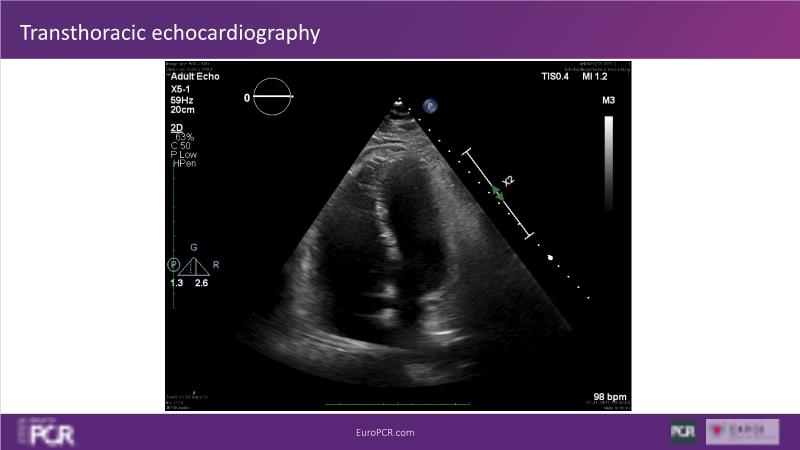

Why mechanical thrombectomy should be considered in the management of acute pulmonary embolism

In this EuroPCR 2024 session, study the case of a patient with high-risk pulmonary embolism and another with intermediate to high-risk pulmonary embolism, delve into discussions on clinical evidence for mechanical thrombectomy in pulmonary embolism, acquire skills to evaluate eligibility for mechanical thrombectomy, and learn how to integrate such technique in local pulmonary embolism patient pathway.